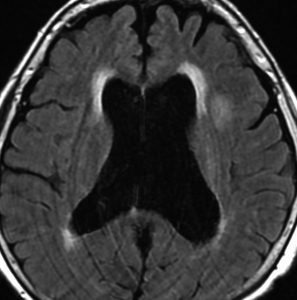

中頭蓋窩・症候性・くも膜のう胞

60代の女性で偶然発見された大きなクモ膜のう胞です。経過とともに少しづつ増大して,ふらつき,眠気,気分の落ち込みなど抑うつ状態となりました。抗うつ薬の投与が開始され増量されましたが精神症状は悪化して何もできなくなりました。おそらく右側頭葉症状として抑うつ症です。内視鏡ですと脳に損傷が生じますから,開頭顕微鏡手術で,クモ膜のう胞を脳底槽へ開窓しました。術後に症状は消失して5年になりますが,抗うつ薬なしで元気にしています。

もしかするとこれは,巨大な choroidal fissure cystかもしれません。